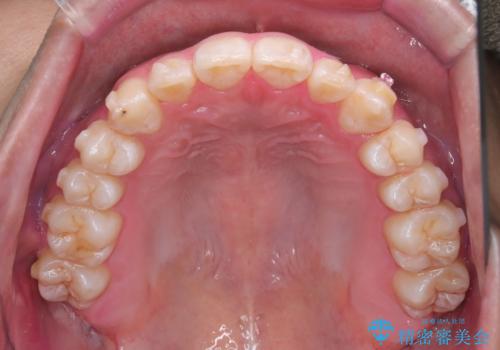

- 八重歯が気になるとのことでご来院されました。お口の中を確認すると、上の前歯がスペース不足で押し出され、少し前に出ている状態でした。抜歯せずに整えるため、奥歯を少しずつ後ろに動かしながら(遠心移動)、歯と歯の間をわずかに削るIPRを行ってスペースを作ることにしました。また、上下の噛み合わせを整えるために2級ゴム(エラスティック)を使用する方針を立てました。

マウスピースを段階的に交換しながら、奥歯を少しずつ後ろへ動かし、八重歯がきれいに並ぶよう調整しました。前歯の突出感を抑えるためにIPRを行い、スムーズに配列。さらに、2級ゴムを活用して噛み合わせも改善しました。治療後は、自然な歯並びになり、笑顔に自信が持てるようになったと喜んでいただきました。